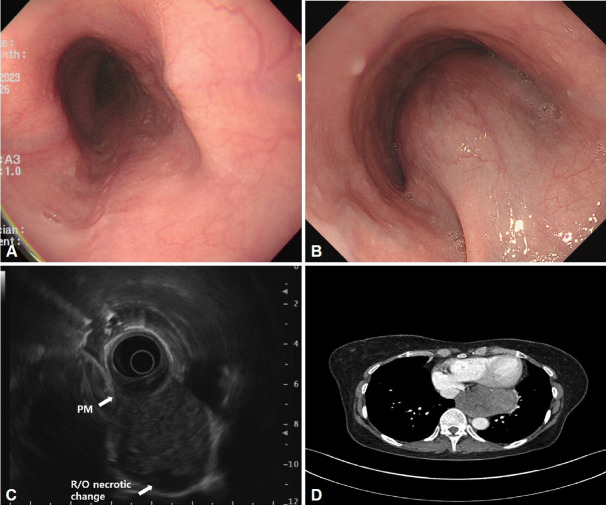

胃肠道间质瘤(gist)是一种罕见的间质肿瘤,主要发生在胃和小肠;而发生在食道的则比较少见。一名54岁妇女因一个月的吞咽困难病史转介至我院。大约5个月前进行的食管胃十二指肠镜检查(EGD)未发现任何特异性发现。然而,在我们医院进行的EGD显示存在一个圆形,突出的病变(大约40×30 mm大小),与正常的粘膜表面覆盖,距离上切牙35-39 cm。胸部电脑断层扫描显示一大块食道肿块。对食管肿块行去核,免疫化学染色诊断为GIST。术后2个月开始给予甲磺酸伊马替尼。术后8个月随访EGD及胸部CT检查,患者病情稳定,未见明显复发。因此,医生应考虑吞咽困难恶化的患者可能有潜在的器质性疾病,如食管间质间质瘤的急性增大,即使近期检查无明显变化。

Gastrointestinal stromal tumors (GISTs) are rare mesenchymal neoplasms that mainly occur in the stomach and small intestine; those arising in the esophagus are rarer. A 54-year-old woman was referred to our hospital with a one-month history of dysphagia. Esophagogastroduodenoscopy (EGD), performed approximately five months earlier, had not revealed any specific findings. However, an EGD performed in our hospital showed the presence of a round, protruding lesion (approximately 40×30 mm in size), with a normal overlying mucosal surface, 35-39 cm from the upper incisor. Chest computed tomography (CT) revealed a large esophageal mass. Enucleation was performed on the esophageal mass, and a GIST was diagnosed using immunochemical staining. Imatinib mesylate administration was initiated two months postoperatively. The patient was stable, without any evident recurrence in the 8-month postoperative follow-up EGD and chest CT examinations. Therefore, physicians should consider that patients with worsening dysphagia may have an underlying organic condition, such as an acute increase in size of an esophageal GIST, even if recent examinations were unremarkable.